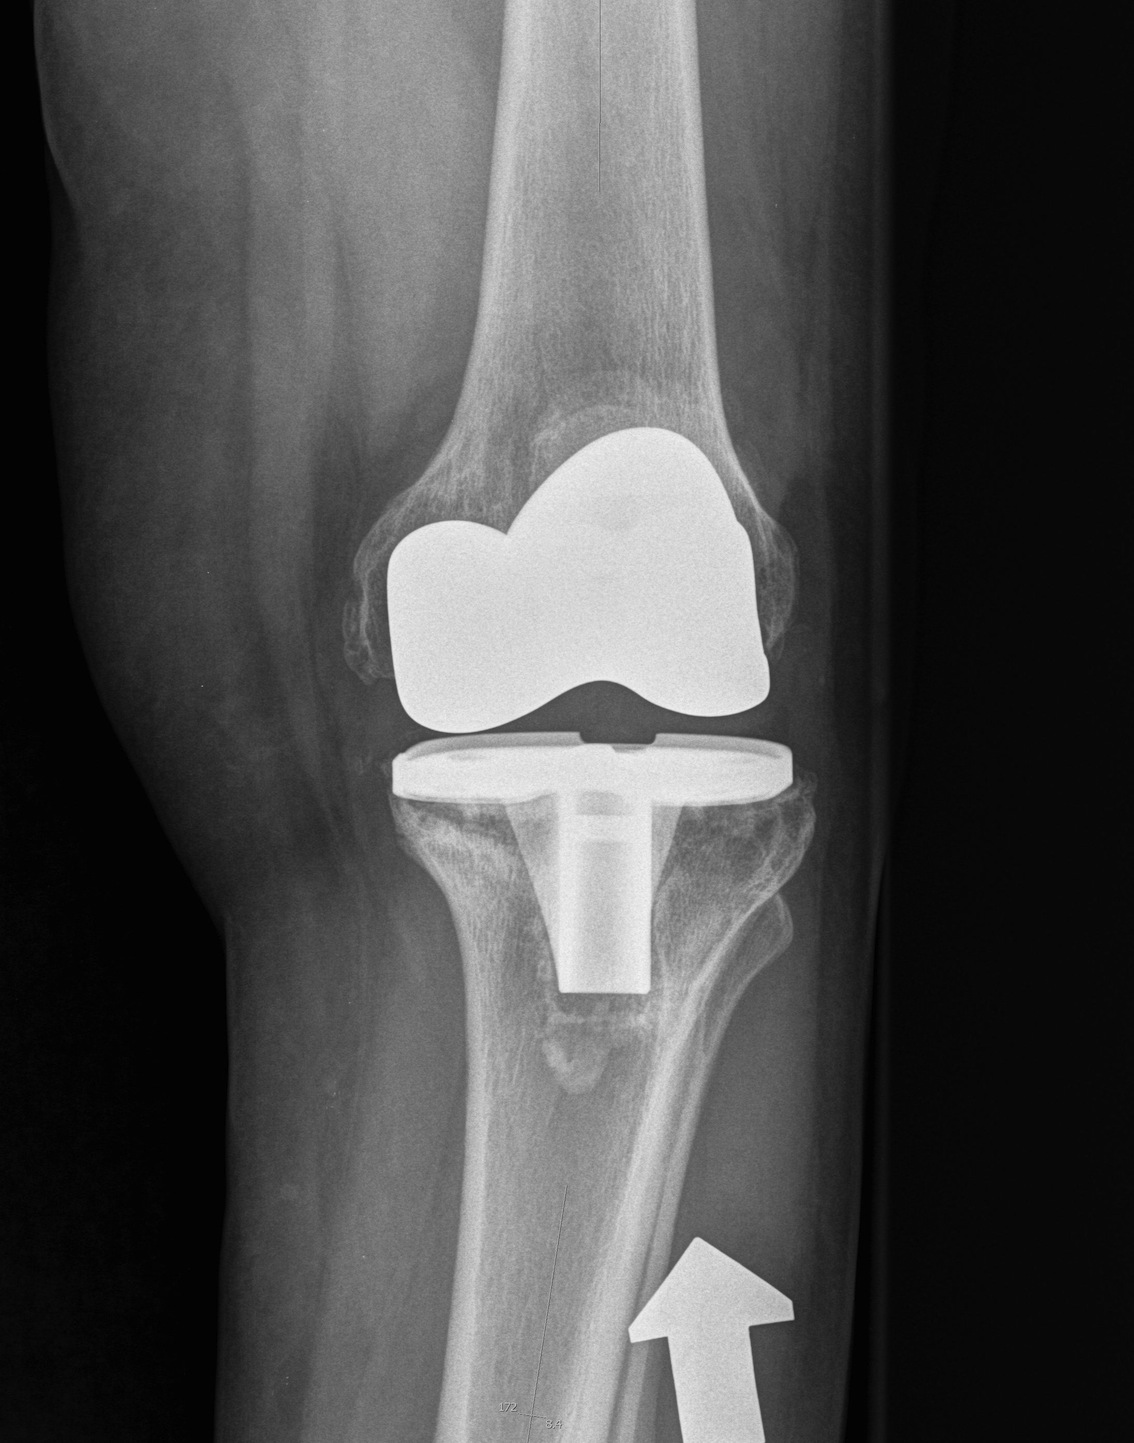

4. Tibial Rotation

Internal rotation of tibial component

- relative external rotation of tibial tubercle

- increase the Q angle

Effects Internal rotation Femur

1. Unequal flexion extension gaps

- alters relative dimensions of posterior condyles in flexion

- tight medially

- loose laterally

- discomfort

- limited flexion

- accelerated poly wear

2. Lateral patella tracking